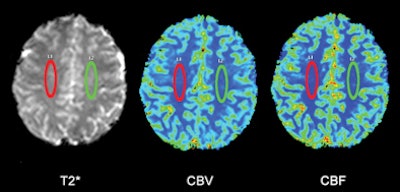

| Regions of interest (ROI) were placed in the white matter of a 38-year-old healthy subject at the level of the semioval centers to avoid arterial and venous structures. ROIs were in the same position and same measurements in all patients with MS and all control subjects. T2* = T2*-weighted MRI; CBV = cerebral blood volume; CBF = cerebral blood flow. Images courtesy of Radiology. |

The researchers used contrast-enhanced MRI to assess blood flow in the brains of both groups. MRI exams were conducted on a 3-tesla scanner (Achieva, Philips Healthcare) with an eight-channel phased-array head coil.

While CCSVI-positive patients showed decreased cerebral blood flow and volume compared with CCSVI-negative subjects, Garaci and colleagues found no significant interaction between MS and CCSVI for any of the blood-flow parameters.